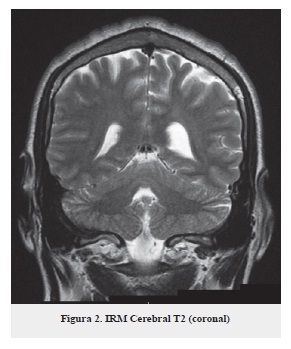

Se plantea como impresión diagnóstica: síndrome cerebeloso en estudio, por tal motivo se ordena resonancia magnética simple y con gadolinio (figuras 1, 2 y 3) no se observan lesiones ocupantes de espacio intra o extra axiales, no hay alteraciones de señal en el parénquima cerebral, cerebro medio o fosa posterior, no hay alteración en el cerebelo.